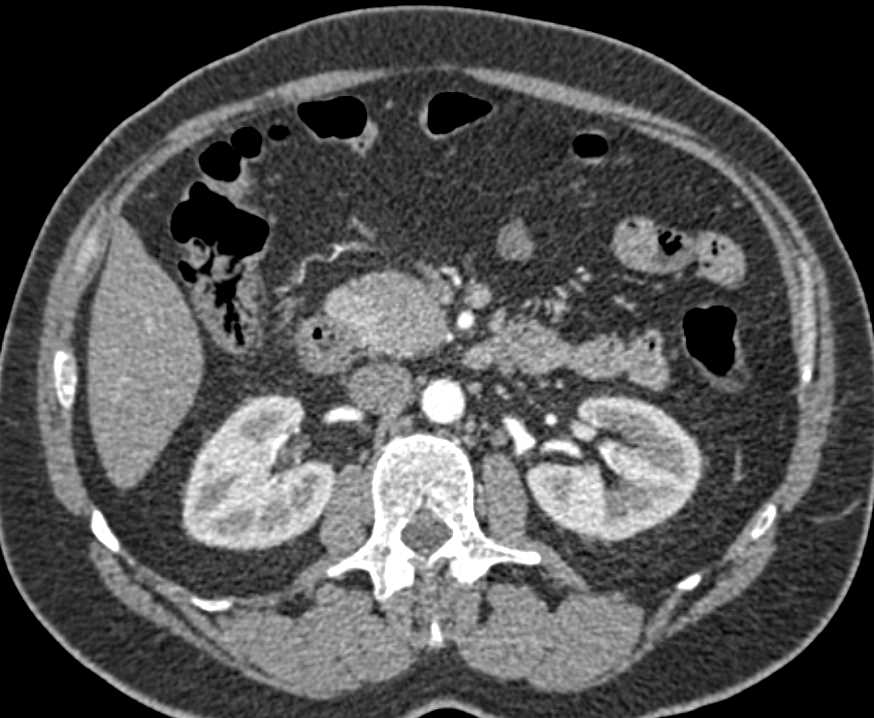

Carcinoma of the Head of the Pancreas